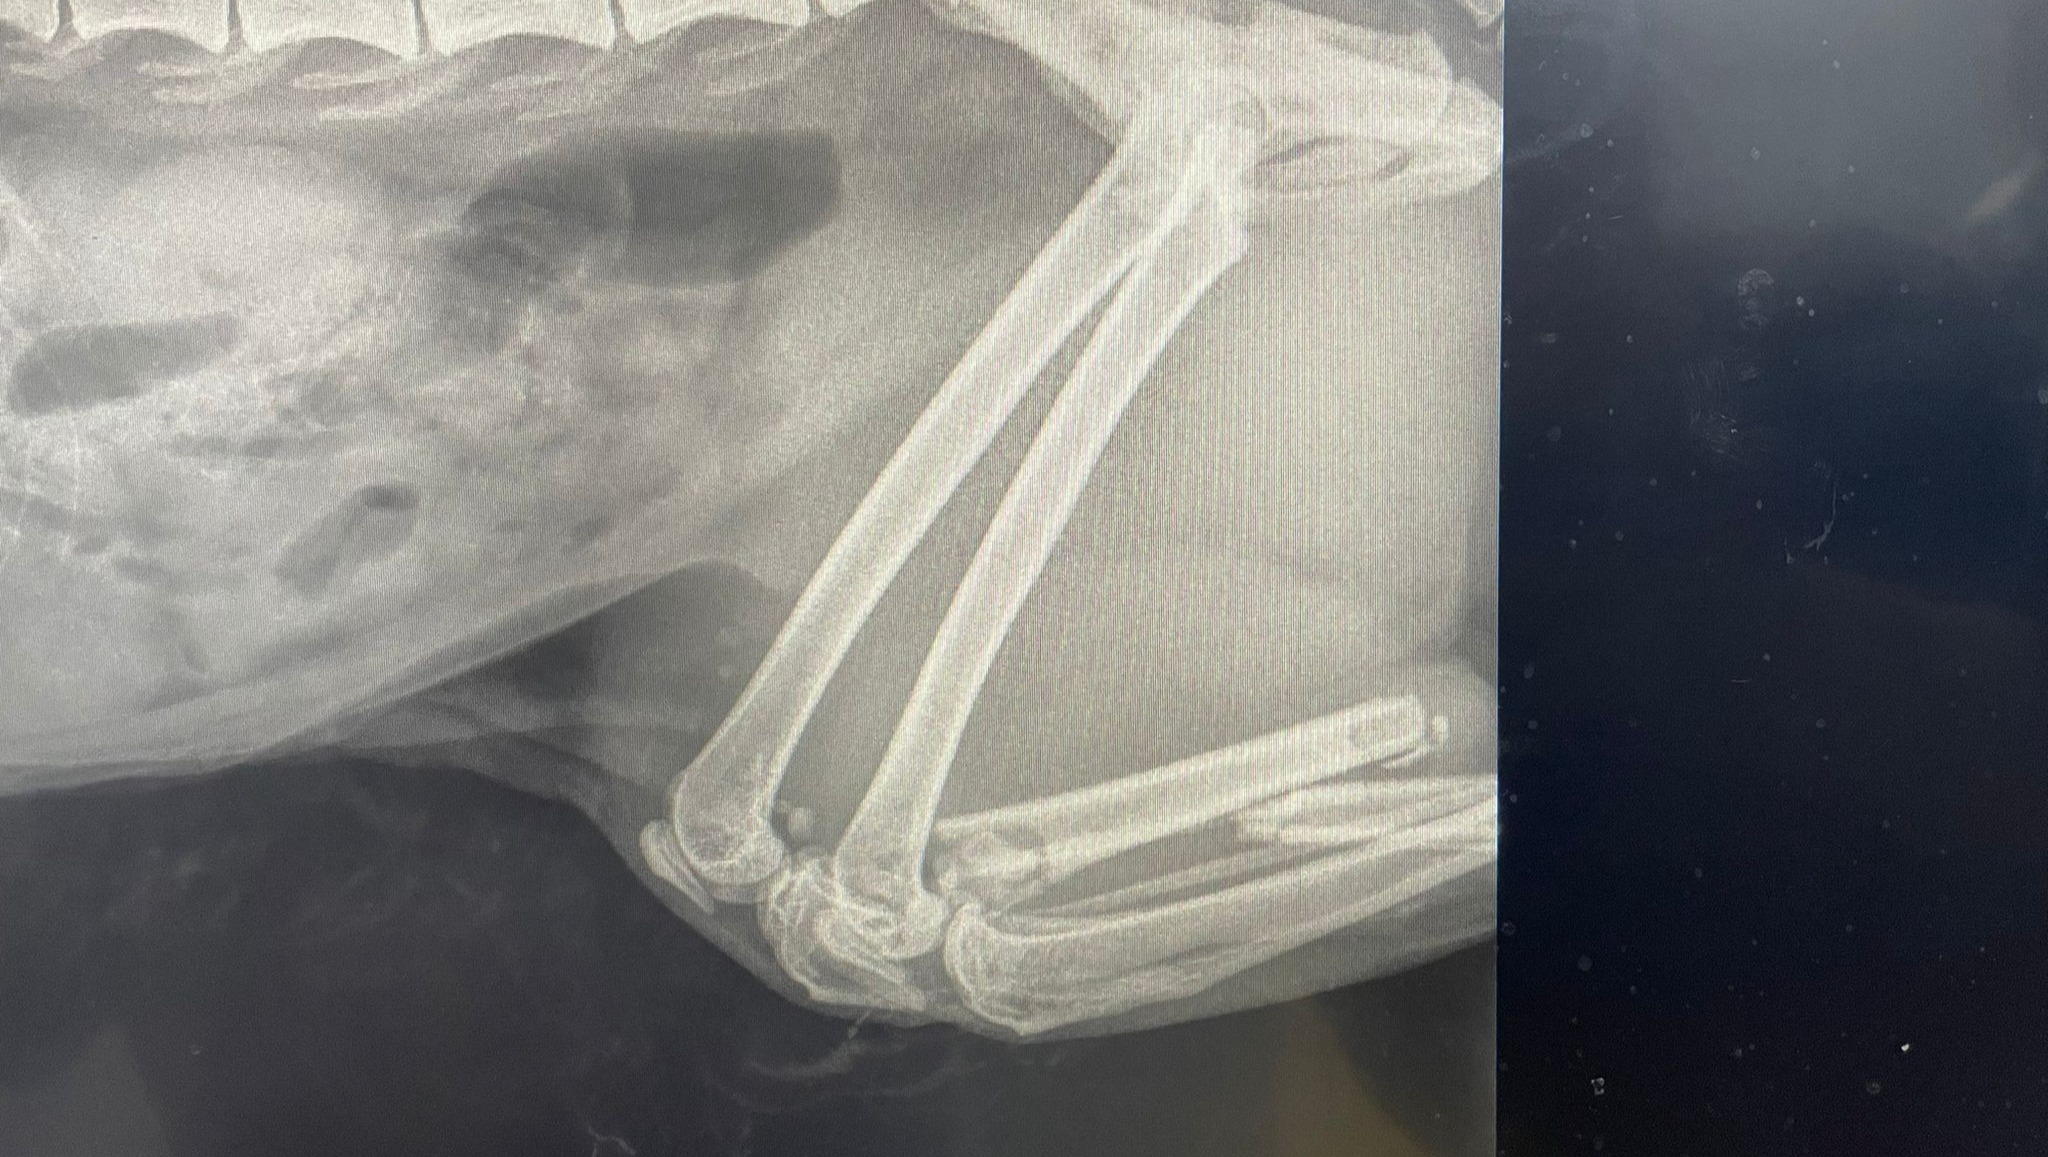

Scarlett ha avuto un brutto incidente, ha bisogno di un operazione e noi in questo momento non possiamo permetterci una spesa cosi alta.

La nostra gatta e' una splendida Maine Coon, ha circa 5 anni, l'abbiamo adottata quando la sua padrona è morta ed è con noi da circa 2 anni.